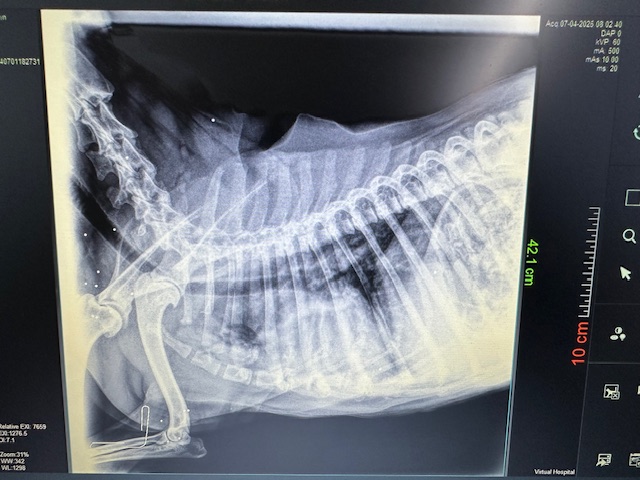

Khari was rescued from the streets in the South. She had pneumonia, tested positive for Erlishia and was anemic. She’s very sweet, friendly and good with dogs. DOB: 9/9/2013